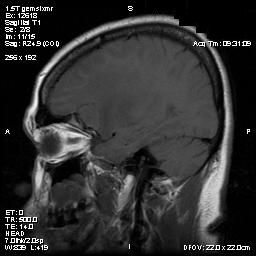

T1-weighed MR images demonstrate an extraaxial, dural based mass involving the right supraorbital region  (Panel A and B). The mass shows homogeneous enhancement  (Panel C). CT scan demonstrates as well as rim calcification (Panel E). On T2-weighed imagers, significant vasogenic edema is demonstrated despite the small size of the lesion and the extraaxial location (Panel D).